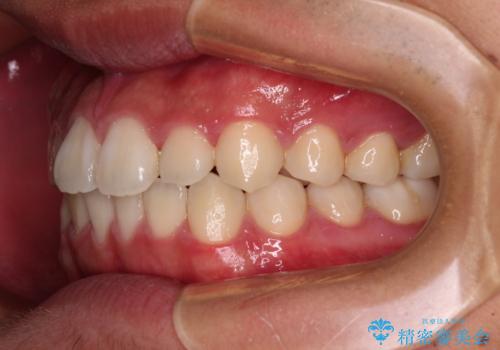

- 20代男性

- インビザライン・ライト

- 上下前歯の叢生を気にして来院された患者様です。

費用を抑え、期間もあまりかけずに治療をしたいとのことで、インビザライン・ライトを用いて矯正治療を行うこととしました。